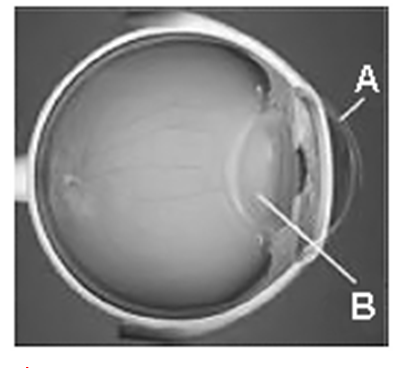

A (PUC SP 2010) O olho humano pode ser entendido como um sistema óptico composto basicamente por duas lentes – córnea (A) e cristalino (B). Ambas devem ser transparentes e possuir superfícies lisas e regulares para permitirem a formação de imagens nítidas. Podemos classificar as lentes naturais de nossos olhos, A e B, respectivamente, como sendo:

- a) convergente e convergente.

- b) convergente e divergente.

- c) divergente e divergente.

- d) divergente e convergente.

- e) divergente e plana.